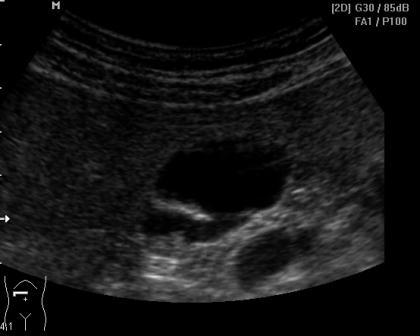

Мужчина 55 лет

1.JPG

1.JPG (15.56 КБ) 548 просмотров

Конкременты?

Лежал он во время осмотра и на животе, и на спине, и на обоих боках и даже постоял, но в сторону дна, в желчном, ничего смещаться не захотело ).

Написала: аденоматозный полип? конкременты? Буду его пересматривать недели через 2-3- может понятней будет.

Видео что-то у меня не идет, а по фото не похоже на конкременты.

Я за образование(стелющийся полип)Не похоже на конкремент